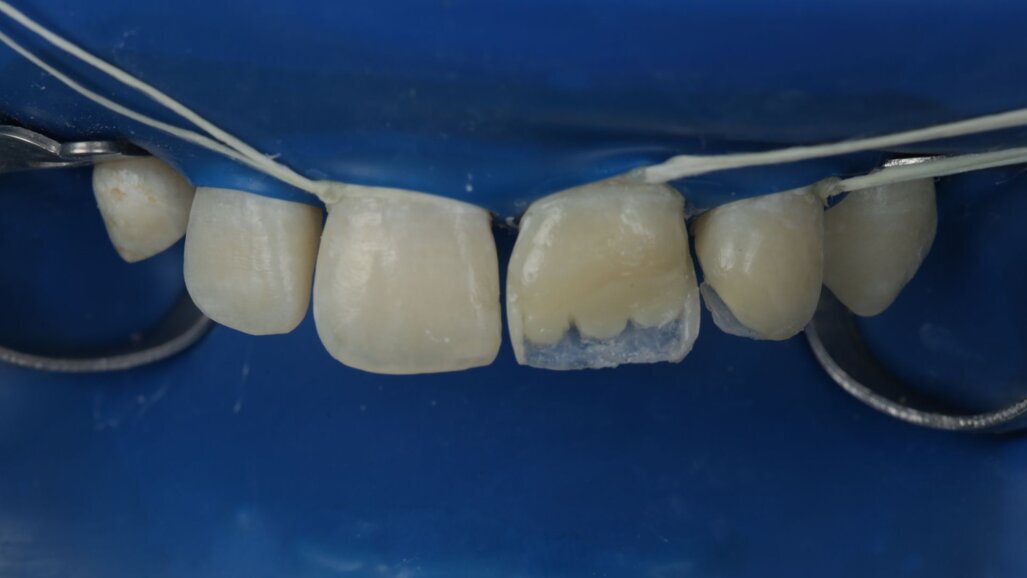

Fig 19-24: Contact build-up with band and wedge